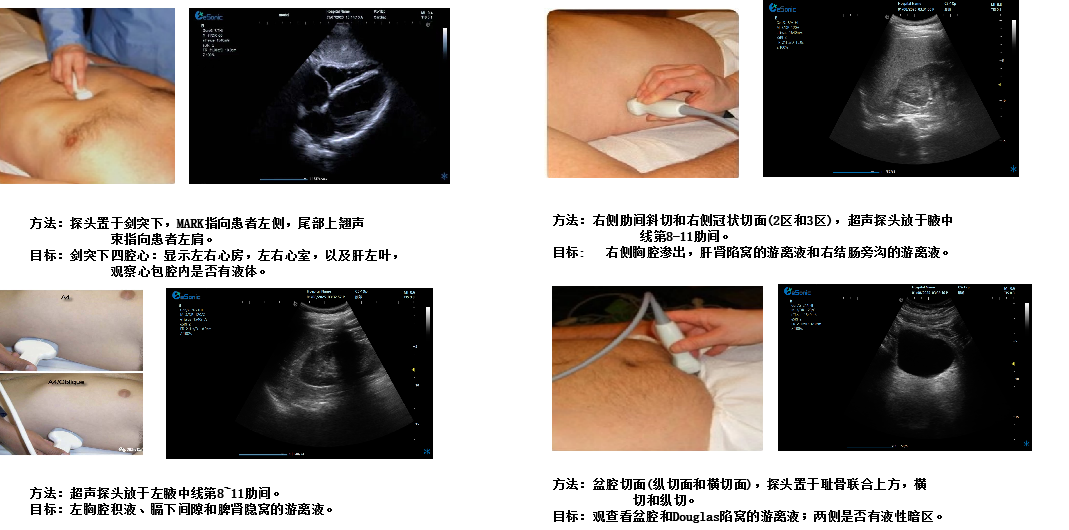

剑突下四腔心切面

image.png

扫查方法:探头置于剑突下,声束指向左肩,稍向上倾斜30°,接近心脏冠状切面

超声声像图:图像近场扇尖处可见肝实质反射,此切面可观察左心房、左心室、右心房、右心室、房间隔、室间隔、二尖瓣、三尖瓣等结构。

创伤评估FAST

重症肺部超声

超声声像图:声束垂直胸膜线时,可见多条A线与胸膜线平行,且等间距。